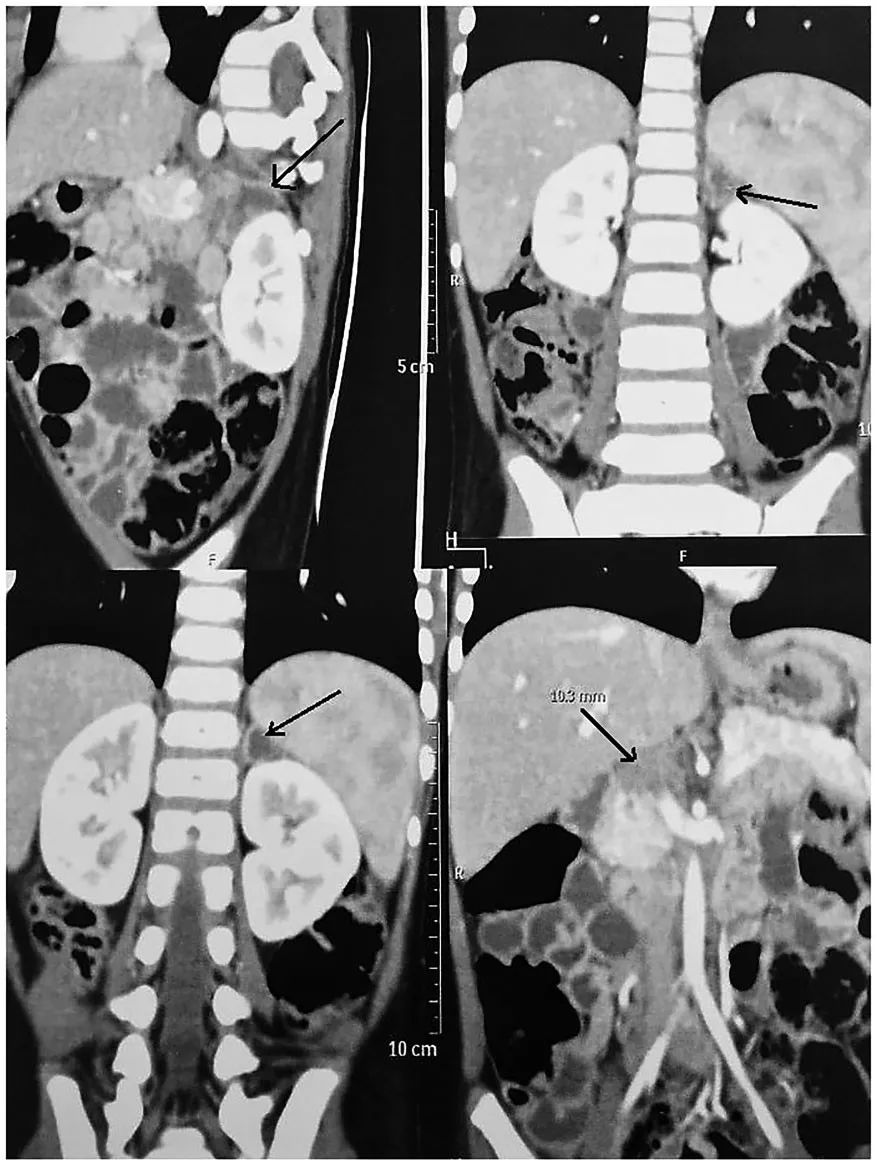

腹部CT显示左肾上腺脓肿1.8×1.1× 2.3厘米,t2呈异源性高信号,t1呈低信号,左肾上腺肿大呈异源性外周增强,门周淋巴结坏死,提示感染病因,结核可能性大。右肾上腺正常。

CT引导下肾上腺脓肿活检,抽吸干酪样物质。结核分枝杆菌对利福平耐药,Genexpert分析阳性。将样本送去培养,鉴定为结核分枝杆菌。